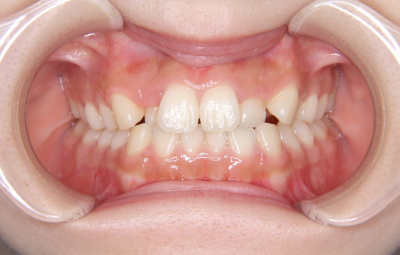

歯科検診で歯並び1にチェックされた場合、「要観察」ということを意味します。 軽度な歯列異常(1〜2歯の反対被蓋や切端咬合など)で経過観察が望ましい状態です。

• 歯並びが少しガタガタしている

• 歯の生え替わり方に異常がある

• 上下の歯がきっちりとかみ合っていない

等の状態であることが多いですが、どの部位が要観察なのかしっかりと確認しておくことが大切です。

学校の歯科検診で歯並び2にチェックされた場合、専門的な診査が必要なことを意味します。 主に、叢生・正中離開などの重度な歯列異常や、反対咬合・上顎前突・開咬などの重度の不正咬合の場合にチェックされることが多いです。